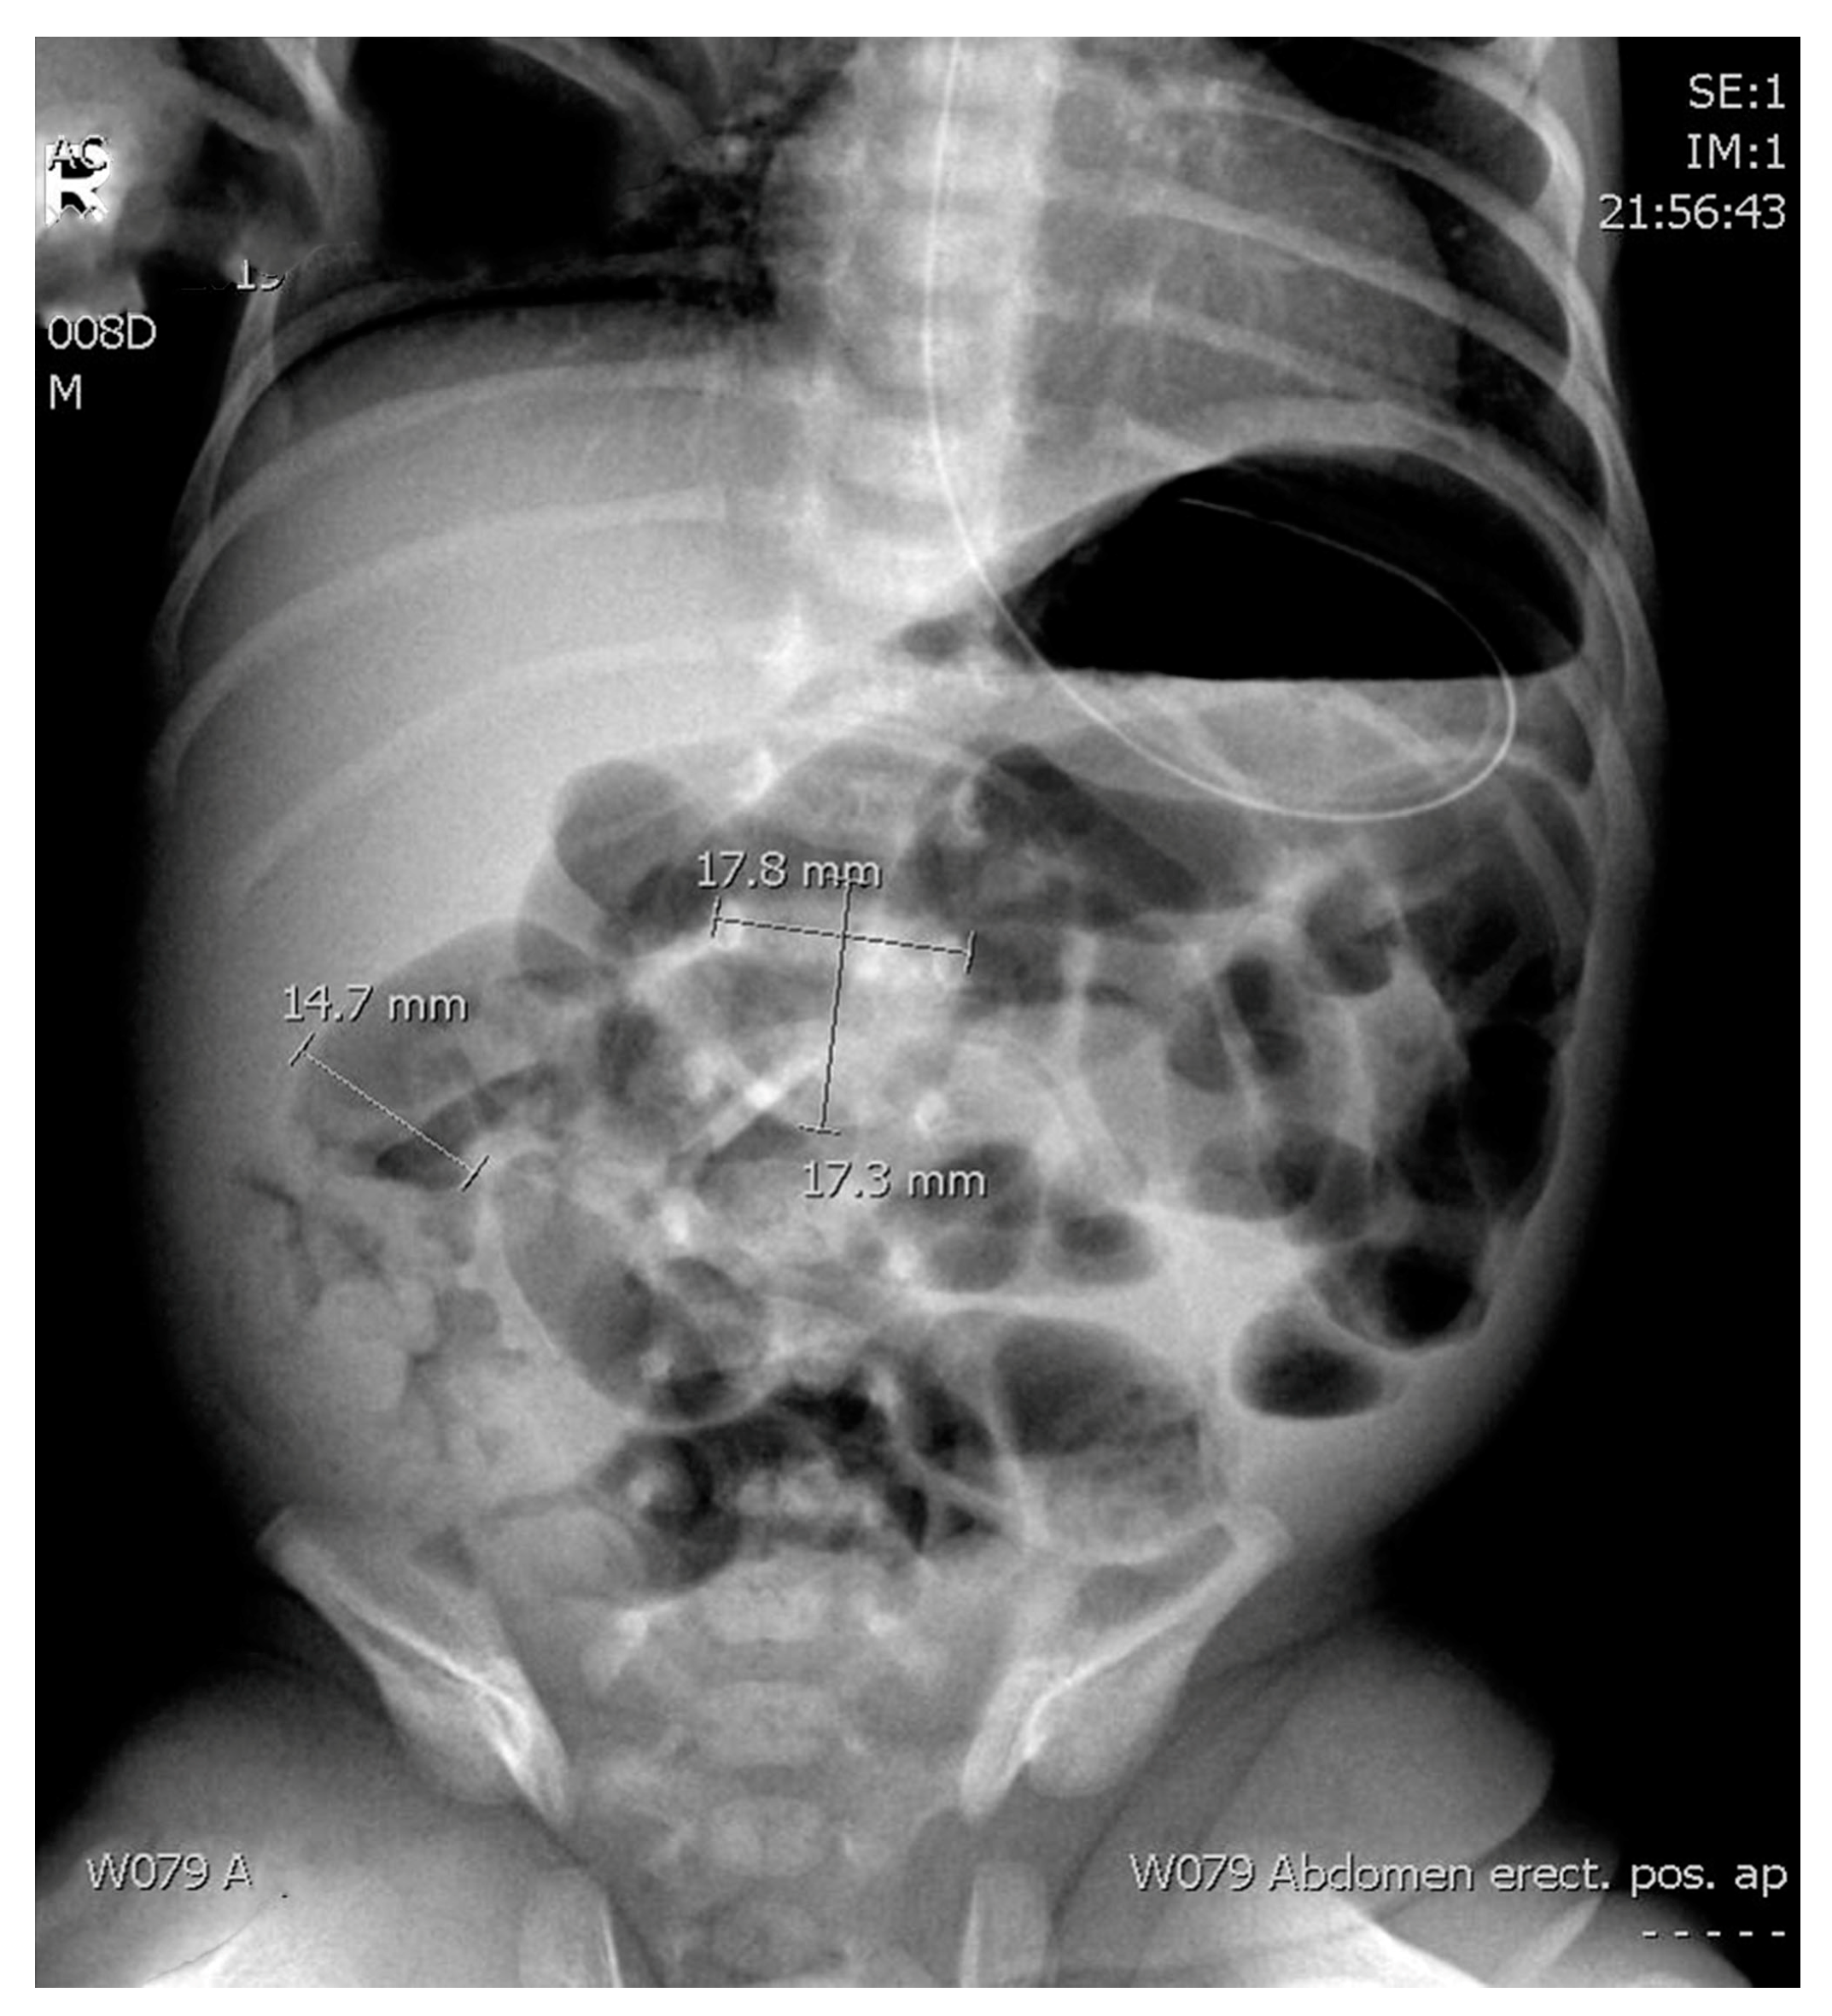

The radiological assessment included ARs (supine anteroposterior projection) obtained as a first radiology method. Only the first abdominal radiographs taken for a patient with suspected necrotizing enterocolitis was re-reviewed for the study purposes. We examined the ratio between the diameter of the most distended intestinal loop (AD) and the diameter of the lateral edges of the first lumbar vertebral body (L1) as previously suggested by Edwards and Martins [6,7] (Figure 2). In addition, we explored the ratio between the upper edge of the first lumbar vertebra and the lower edge of the second one, including the disc space (L1–L2) (Figure 2).

Figure 2.

Supine anteroposterior projection abdominal radiography of a preterm infant with necrotizing enterocolitis with the measurement mode shown.

- AD—Diameter of the most distended intestinal loop (14.7 mm).

- L1—Diameter of the lateral edges of the first lumbar vertebral body (17.8 mm).

- L1–L2—The ratio between the upper edge of the first lumbar vertebra and the lower edge of the second one, including the disc space (17.3 mm).